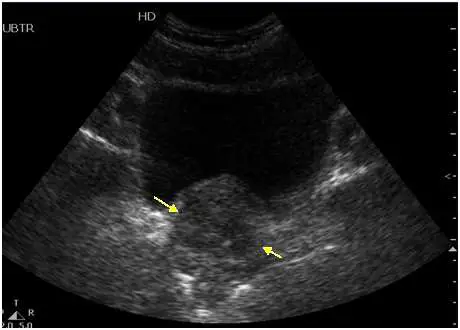

骨盆腔超音波掃描如下圖,箭號所指為何?

影像為男性骨盆腔超音波掃描,標記「UBTR」(上方)及「HD」字樣,使用經腹部(transabdominal)途徑掃描。影像中可見:

- 上方大型無回音構造:為充盈的膀胱(urinary bladder),呈均質無回音(anechoic),提供良好的聲學視窗

- 兩個黃色箭號:

- 左側黃色箭號(較大,指向膀胱後下方):指向一個中等回音、質地均勻的實質性構造,位於膀胱直接後方,輪廓清楚,形態呈半圓形或栗子形——此為攝護腺(prostate)

- 右側黃色箭號(較小,偏外側):指向攝護腺基底部後上方的管狀/囊狀低回音構造——此通常對應儲精囊(seminal vesicles)或攝護腺上極

- 攝護腺特徵:呈等回音至低回音(isoechoic to hypoechoic)實質構造,邊界清楚,位於膀胱正下方/後方,前方為恥骨聯合(pubic symphysis)

根據影像中箭號的主要指向及其解剖位置,